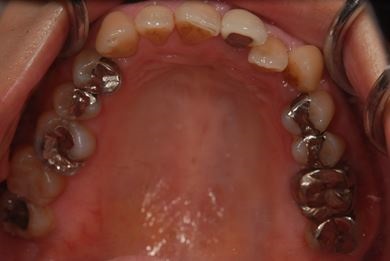

セラミック治療+ラミネートベニア治療

| 主訴 | 虫歯を白い詰め物で治療したい。全体的に歯の色が気になるので、ホワイトニングをしたい。ホワイトニングの効果がなければ、セラミック治療を受けたい。 | ||||||||||||||||||||||||||||||||

| 治療方針 | セラミック治療にて、審美的回復を行う。 | ||||||||||||||||||||||||||||||||

| 治療内容 | ジルコニアオールセラミッククラウン1本(オールセラミック用土台1本)、オールセラミッククラウン9本(オールセラミック用土台1本)、オールセラミックラミネートベニア11本 | ||||||||||||||||||||||||||||||||